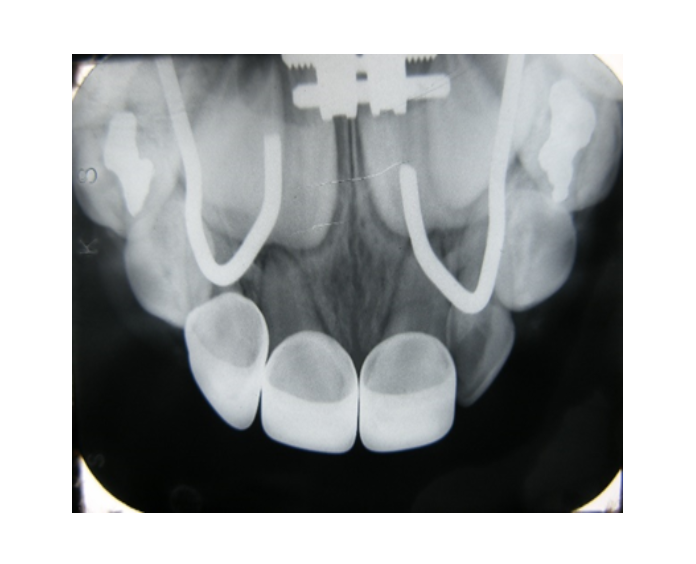

Mordida cruzada posterior bilateral